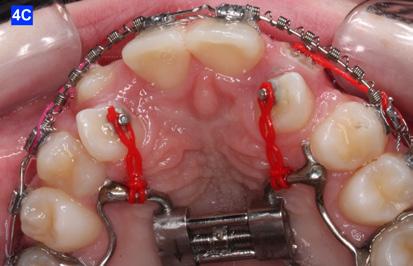

The maxillary cuspids were erupting mesially to the lateral incisors, with very little space to accommodate both teeth without an odontectomy. The expansion was continued (1/4 turn 2x per week), and an attempt was made to create more space for erupting cuspids with an open coil spring (OCS) – between the central incisors and the cuspids (Molar distalization spring, a .010 x .045 - Ortho Organizers). The OCS was measured and cut 4.0 mm longer than the available space. The maxillary arch wire was a .018 SS. An elastomeric chain (EC) was attached from the Hyrax to the lingual button on the lateral incisors. It was necessary to first pull the lateral incisors away from the alveolar process to prevent the break down of the buccal cortical bone around the cuspids (Figure

B, C).

4-A, Figure 3A: The patient transferred to our office, frontal view Figure 3B: The patient transferred to our office, maxilla, occlusal view Figure 3C: The patient transferred to our office, mandible, occlusal view Figure 4A: OCS, frontal view Figure 4B: Hyrax, occlusal view Figure 4C: Retraction of maxillary lateral incisors